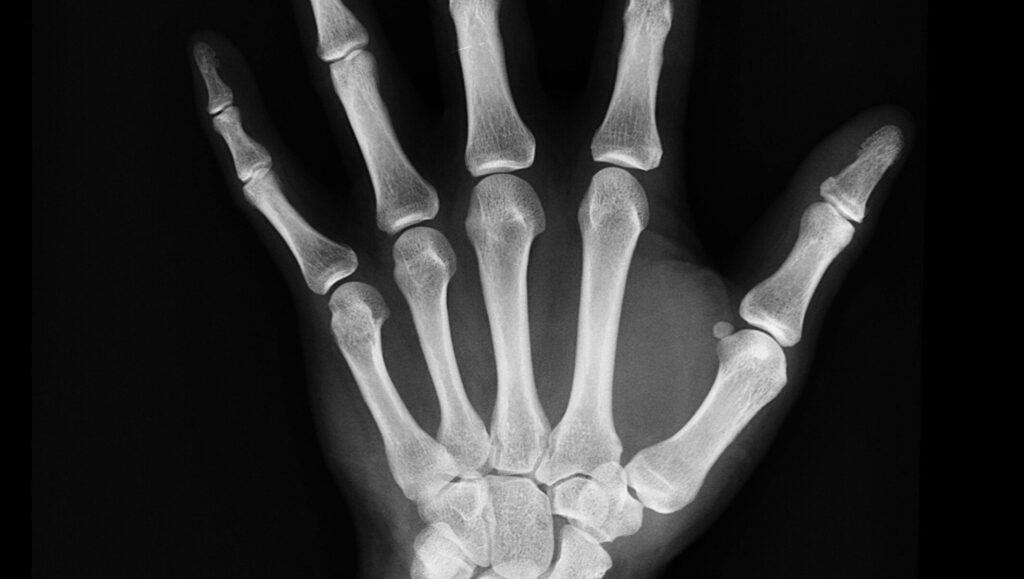

Nivelul de cunoștințe anatomice și chirurgicale descris în document depășește cu mult ceea ce istoricii credeau anterior că este posibil pentru acea perioadă. Autorii descriu tehnici pentru oprirea sângerărilor, tratarea infecțiilor, închiderea rănilor sau gestionarea fracturilor osoase.